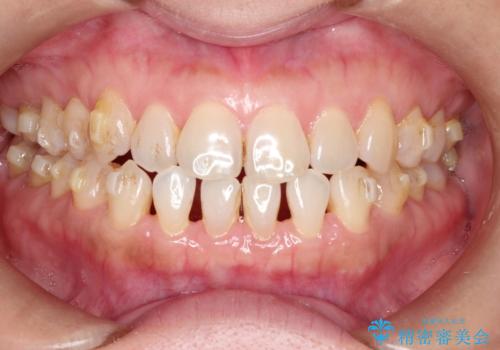

前歯の隙間 インビザラインによる目立たない成人矯正

- 前歯の隙間を気にされて来院されました。

インビザラインにて、目立たずに矯正治療を行うこととしました。

歯と歯の間にある隙間を閉じるのは、インビザラインでもしっかり治療できます。